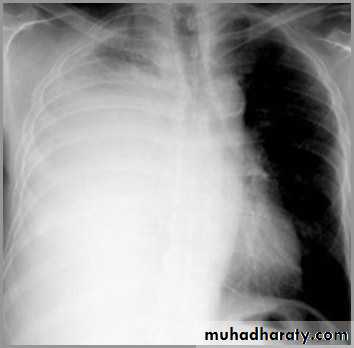

Differentiating the Causes of an Opacified Hemithorax

Atelectasis of an entire lungA large pleural effusion

It acts like a massPushing the heart and trachea away from the side of opacification

Pleural effusion